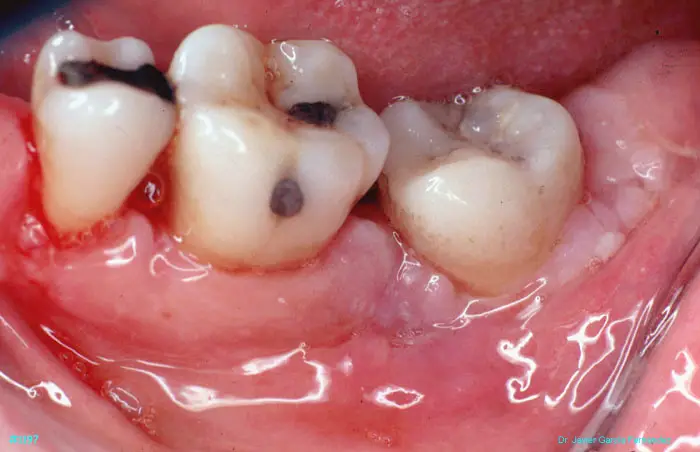

Atlas of Surgical Techniques in Periodontics. Chapter III. Atlas de Técnicas Quirúrgicas en Periodoncia